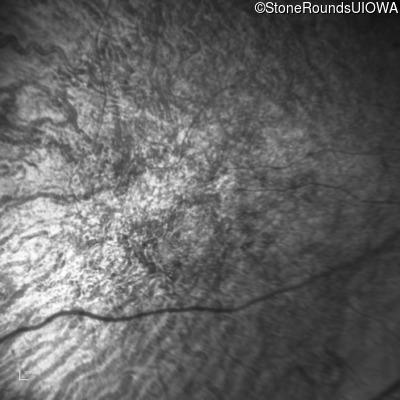

Age at visit: 41 years

This 41 year old man first came to medical attention at age 18 months when exotropia and amblyopia of his right eye were discovered. At age 11 vitreous strands and retinal vascular sheathing were seen. He has had poor night vision and constricted visual fields since his late teens. Later, at age 44 a traction retinal detachment was noted in his left eye and was treated with a scleral buckle.